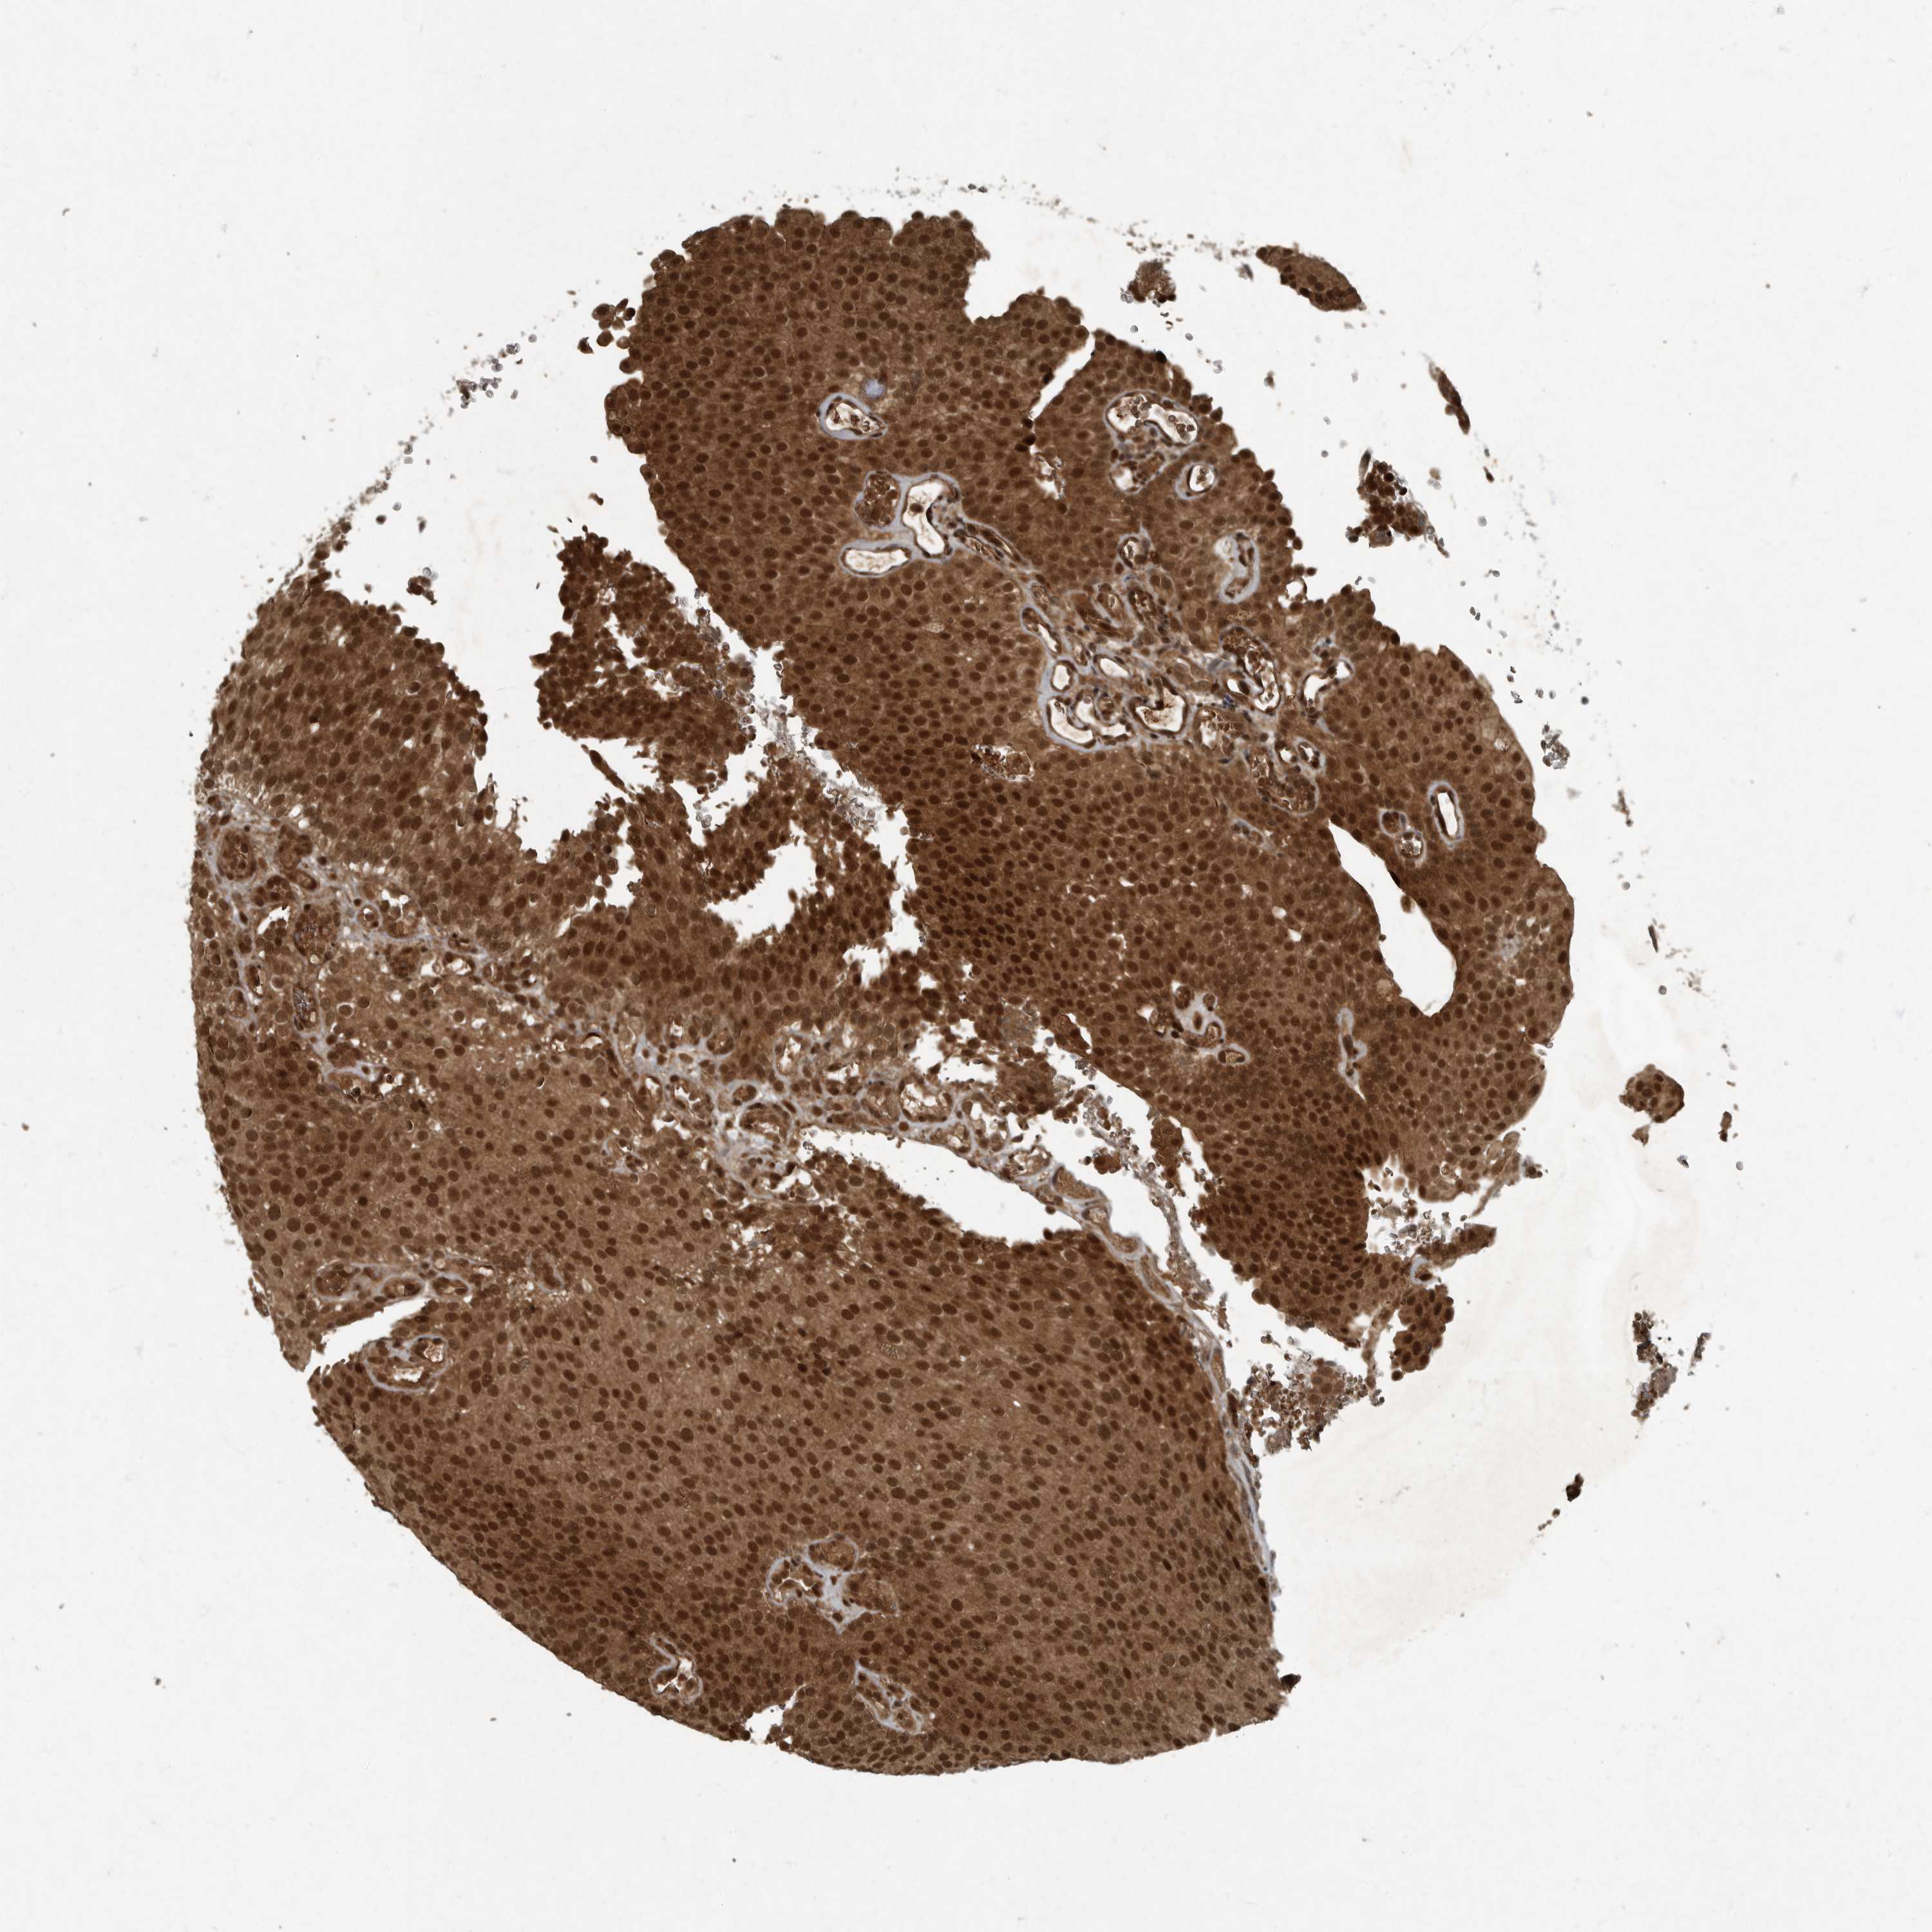

UROTHELIAL CANCER - Protein expressioni

A mouse-over function shows sample information and annotation data. Click on an image to view it in a full screen mode. Samples can be filtered based on level of antibody staining by selecting one or several of the following categories: high, medium, low and not detected. The assay and annotation is described here.

Note that samples used for immunohistochemistry by the Human Protein Atlas do not correspond to samples in the TCGA dataset.

Antibody stainingi

Antibody staining in the annotated cell types in the current human tissue is reported as not detected, low, medium, or high, based on conventional immunohistochemistry profiling in selected tissues. This score is based on the combination of the staining intensity and fraction of stained cells.

Each image is clickable and will lead to virtual microscopy that enables deeper exploration of all samples and also displays staining intensity scores, fraction scores and subcellular localization as well as patient and tissue information for each sample.

CAB022326

Urothelial carcinoma, High grade

Urothelial carcinoma, Low grade

Adenocarcinoma, NOS